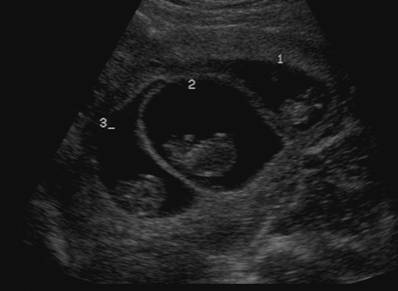

Σε πελάγη ευτυχίας πλέει μια οικογένεια από το Ηράκλειο, καθώς γεννήθηκαν απολύτως υγιή τρίδυμα αγοράκια που τρέφονταν από τον ίδιο πλακούντα.

Σήμερα τα ξημερώματα, η 33χρονη γυναίκα, έφερε στον κόσμο τα τρία υγιέστατα αγοράκια, βάρους 1200 ως 1400 γραμμαρίων. Τον τελευταίο χρονικό διάστημα η έγκυος  νοσηλευόταν στο Πανεπιστημιακό Νοσοκομείο Ηρακλείου στη Μαιευτική- Γυναικολογική Κλινική. Τα έμβρυα βρίσκονταν σε τρεις σάκους αλλά τρέφονταν από τον ίδιο πλακούντα. Μια περίπτωση σπάνια, για την οποία υπήρχε πάντα ο κίνδυνος της επιπλοκής, μιας και σε τέτοιες εγκυμοσύνες είναι πιθανή η «υποκλοπή αίματος» του ενός εμβρύου από τα άλλα.

Τα μωράκια γεννήθηκαν πρόωρα μεν σε καλή κατάσταση δε. Όπως εξηγεί ο κ. Σηφάκης, μιλωντας αποκλειστικά στο CretePlus.gr: «η περίπτωση αυτή είναι πολύ σπάνια, καθώς τα μωρά τρέφονταν και αναπτύσσονταν από τον ίδιο πλακούντα. Πρόκειται για μονοζυγωτική, μονοχοριακή, τριαμνιακή κύηση.

Υπήρχε συνεχώς ο κίνδυνος της υποκλοπής αίματος εμβρύου από έμβρυο. Δηλαδή μπορούσε να υπάρξει άνιση παροχή του αίματος από τον πλακούντα στα τρία διαφορετικά έμβρυα, με αποτέλεσμα το ένα μωρό να γίνεται παθολογικά μεγάλο και το άλλο (ή τα άλλα δύο) να εκδηλώσει σοβαρή υπολειπόμενη ανάπτυξη, με συνολικά κακή έκβαση της κύησης»

Σήμερα λοιπόν τα μεσάνυχτα, το ιατρικό επιτελείο που παρακολουθούσε την εγκυμονούσα προχώρησε σε καισαρική για να έρθουν στον κόσμο τα μωράκια, παρά το γεγονός πως η εγκυμοσύνη ήταν στην 30η εβδομάδα. Είχε προηγηθεί αυτόματη ρήξη των υμένων στον ένα από τους τρείς σάκους και αναπόφευκτα ακολούθησαν πρόωρες συστολές μήτρας.